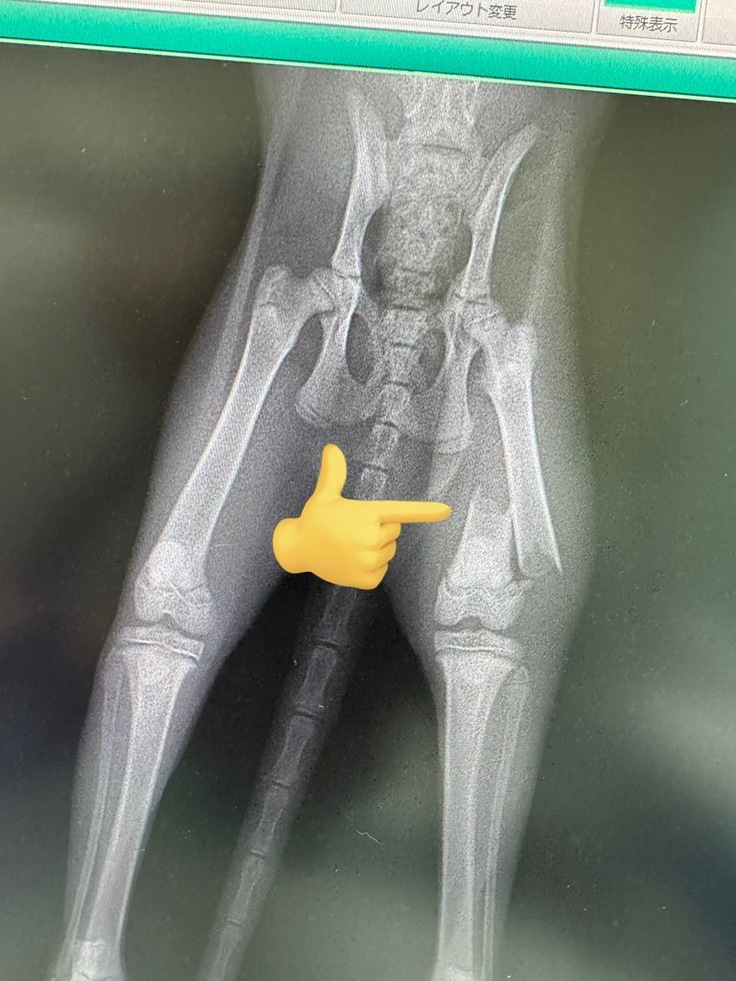

診察の結果左後脚の骨折が判明しました。

8月31日に手術をして無事成功しましたがしばらくは入院になります。